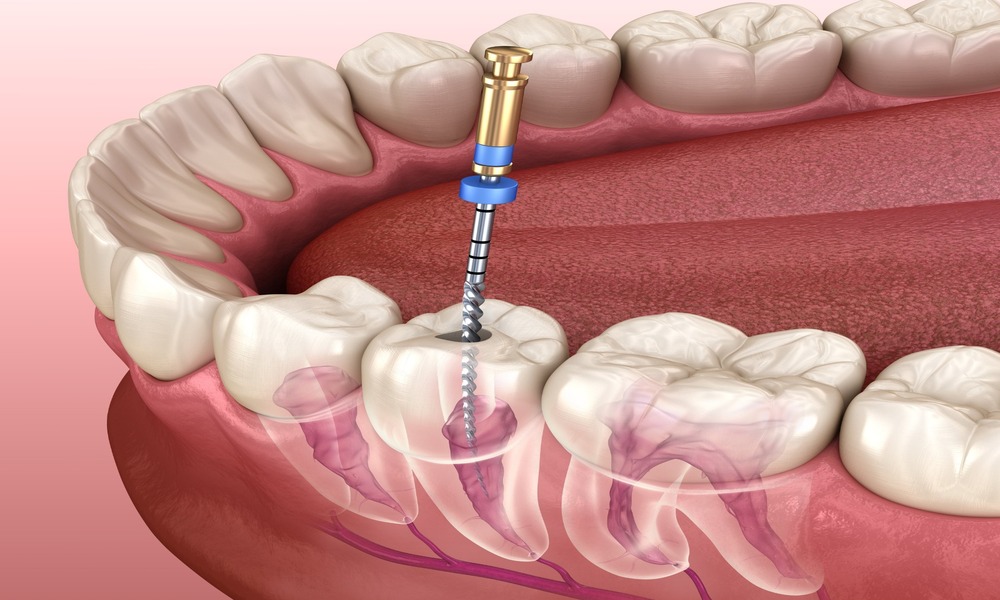

What Happens During a Second Root Canal

A second root canal procedure involves reopening the tooth, removing the previous filling material, and thoroughly cleaning the canals again. The dentist will locate any missed or infected areas, disinfect the canals, and reseal them properly.

In some cases, advanced imaging or magnification tools are used to ensure complete cleaning. After the procedure, a new crown is usually placed to protect the tooth.